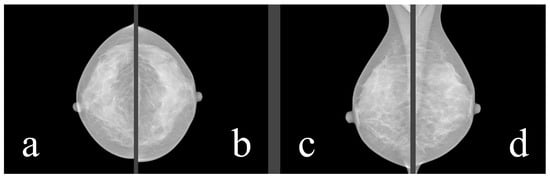

For our purposes, breast composition is the first important step. In the older BI-RADS edition, the assignment was based on the four ACR (American College of Radiology) categories, which were based on the density of fibroglandular tissue in the breast (Figure 3, Table 1). However, in the 2013 edition, the standard was changed to categories a–d (Table 2), which consider the likelihood that a mass may be obscured by fibroglandular tissue.

Figure 3. ACR standardized breast density. Source: [12].